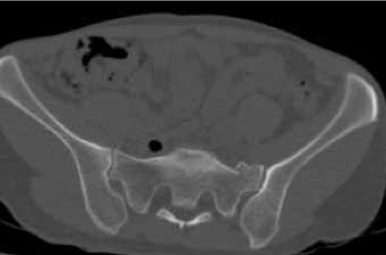

Как основной метод лечения, без стабилизации переднего полукольца таза, остеосинтез заднего комплекса винтами (рис. 1) выполнен у 196 пациентов. Из них открытые переломы встречались у 15 (7,7 %) и были представлены в 12 случаях разрывами мочевого пузыря, в 3 - разрывами уретры. У 161 пациента отмечались повреждения типа В, у 35 - типа С, у 124 - унилатеральные, у 72 - билатеральные. Повреждения переднего полукольца таза были представлены у 3 пациентов разрывами лонного сочленения, у 193 - переломами ветвей лонных костей. Разрыв КПС как основное повреждение заднего комплекса таза встречался у 75 пациентов, переломы подвздошной кости и крестца - у 121.

Рисунок 1. Рентгенограммы пациентки Б. 31 года, повреждение тазового кольца 61-В1: a) до реконструкции; b) после остеосинтеза заднего комплекса винтом с каналом 7,3 мм

Как правило, изолированно остеосинтез илеосакральными винтами заднего комплекса использовался у пациентов без смещения отломков или с незначительным смещением. В случае смещений, превышающих 2,5 см по длине и 1,0 см по ширине, всегда требовалась репозиция и дополнительная фиксация переднего полукольца таза. При этом вставал вопрос об очередности этапов оперативного вмешательства. Какое полукольцо таза восстанавливать в первую очередь: переднее или заднее? Репозиция и стабильная фиксация отломков переднего комплекса способствовала восстановлению правильных взаимоотношений задних отделов таза при горизонтальной или ротационной нестабильности, что значительно облегчало проведение транскутанного остеосинтеза заднего комплекса. В случае повреждений от сдвига или при смешанном механизме, когда имелось вертикальное или заднее смещение, в первую очередь восстанавливали заднее полукольцо, а затем уже переднее, так как в противном случае возникали проблемы при репозиции переднего комплекса.